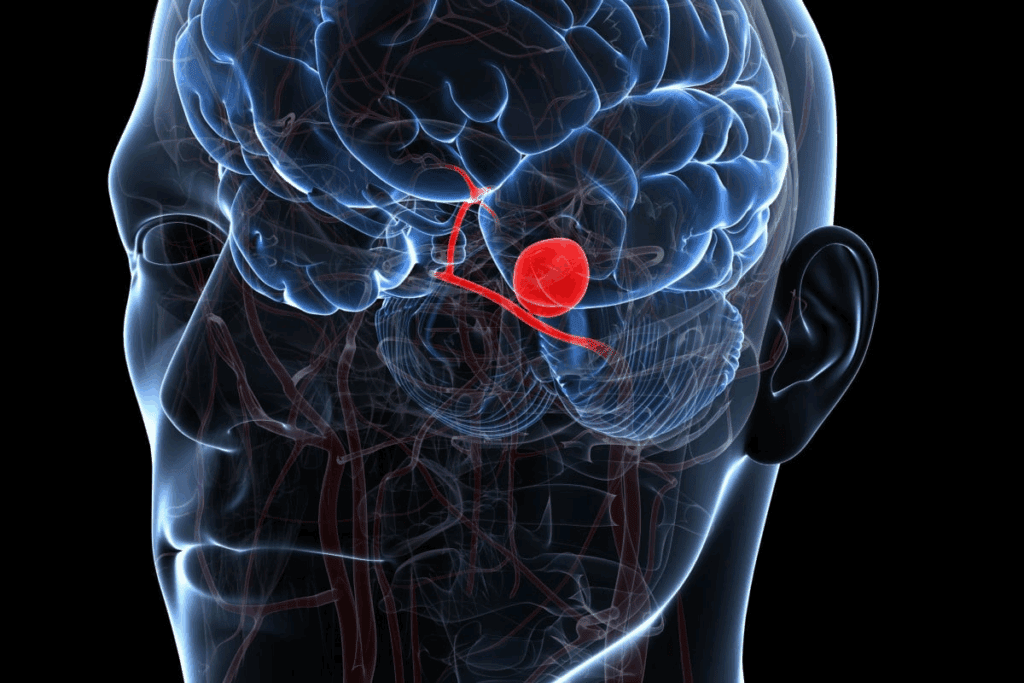

The Concept of Embolization

Embolization blocks blood flow into an aneurysm. In aneurysm treatment, it involves using platinum coils to promote clotting and seal the aneurysm.

This method is minimally invasive. A catheter is used to reach the aneurysm. Once there, the coils are deployed, filling the aneurysm and inducing clotting. This seals the aneurysm, preventing rupture.

How Coils Create Clotting and Seal Aneurysms

The coils used in aneurysm coiling are made of platinum. This material is safe for use in the body. When deployed, the coils help blood clot around them.

As the clot forms, it seals the aneurysm. This prevents blood from entering the sac and reduces the risk of rupture. Coils have been shown to be highly effective in treating aneurysms, reducing the risk of rebleeding and complications.